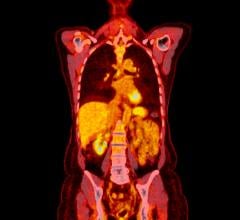

“For some patients with head and neck cancer, removal and pathological examination of lymph nodes draining a primary tumor is an important diagnostic evaluation,” said Libero Marzella, M.D., Ph.D., director of the division of medical imaging products in the FDA’s Center for Drug Evaluation and Research. “To use Lymphoseek, doctors inject the drug into the tumor area and later, using a handheld radiation detector, find the sentinel lymph nodes that have taken up Lymphoseek’s radioactivity.”

For this new indication, Lymphoseek’s safety and effectiveness were established in a clinical trial of 85 patients with squamous cell carcinoma of the lip, oral cavity and skin. All patients were injected with Lymphoseek. Surgeons subsequently removed suspected lymph nodes — those identified by Lymphoseek and those based upon tumor location and surgical practice — for pathologic examination. Results showed that Lymphoseek-guided sentinel lymph node biopsy accurately determined if the cancer had spread through the lymphatic system.